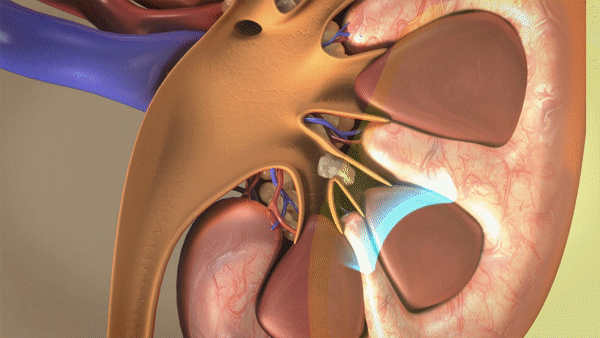

ESWL là phương pháp loại bỏ sỏi duy nhất mà hoàn toàn không xâm lấn đến bệnh nhân, là phương pháp điều trị phổ biến đối với sỏi tiết niệu nhỏ, đơn độc, không biến chứng. Nguyên lý tán sỏi ngoài cơ thể là sử dụng thiết bị tạo sóng xung kích tập trung vào viên sỏi và phá hủy viên sỏi này thành nhiều mảnh nhỏ, các mảnh vụn của sỏi sau đó được đào thải qua đường tiểu.

Nguồn tạo sóng xung kích với 2 nguồn năng lượng là thuỷ lực và điện từ đảm bảo năng lượng nhất quán, cường độ đáng tin cậy giúp tăng khả năng phá vỡ sỏi, hạn chế nguy cơ phải tán sỏi lại.